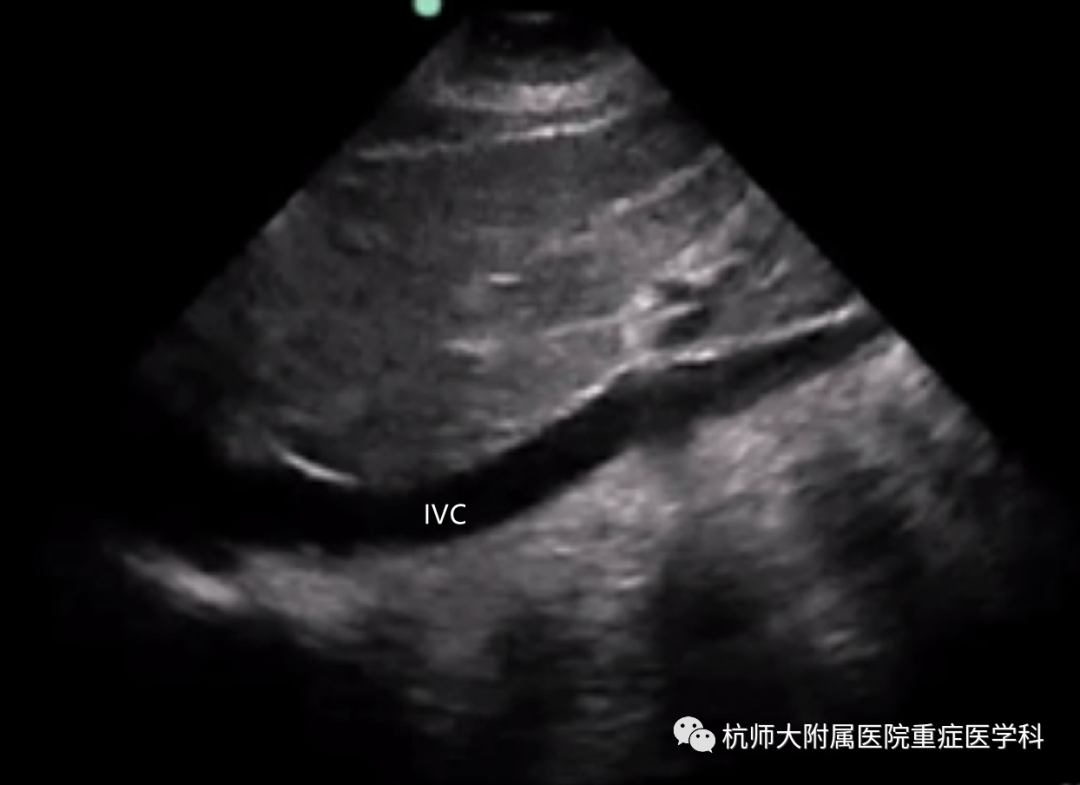

h.剑突下下腔静脉长轴切面:位置选择:剑突下超声探头标记点朝向头侧;操作中(1)摇:在剑突下四腔切面,先将右心房摇至屏幕正中;(2)转:逆时针旋转超声探头90°,完整显示剑突下下腔静脉。

什么是超声容积探头重症心脏超声图像的获取_https://www.jmylbn.com_新闻资讯_第27张什么是超声容积探头重症心脏超声图像的获取_https://www.jmylbn.com_新闻资讯_第28张

主要评估内容:下腔静脉直径;下腔静脉变异度。

b.剑突下下腔静脉切面:主要测量下腔静脉直径、下腔静脉膨胀指数和下腔静脉吸气塌陷指数。